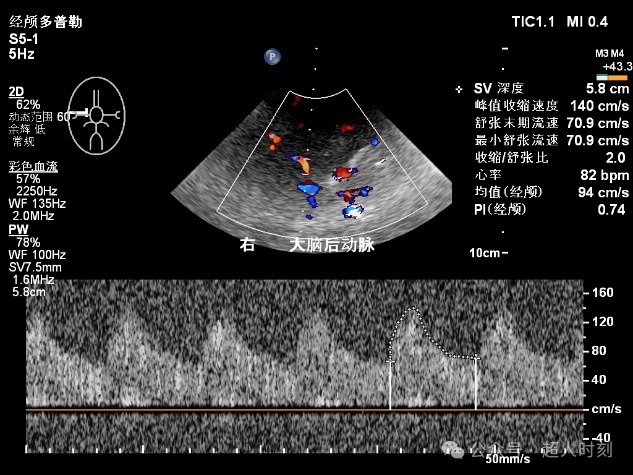

图5e 左大脑中动脉狭窄频谱(VP:178cm/s)